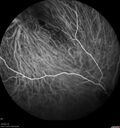

Severe NPDR with non-perfusion on FA15 views64 year old man with 20/32 vision in both eyes and mild blurring. FA shows non-perfusion but no proliferation

Severe NPDR with non-perfusion on FA14 views64 year old man with 20/32 vision in both eyes and mild blurring. FA shows non-perfusion but no proliferation